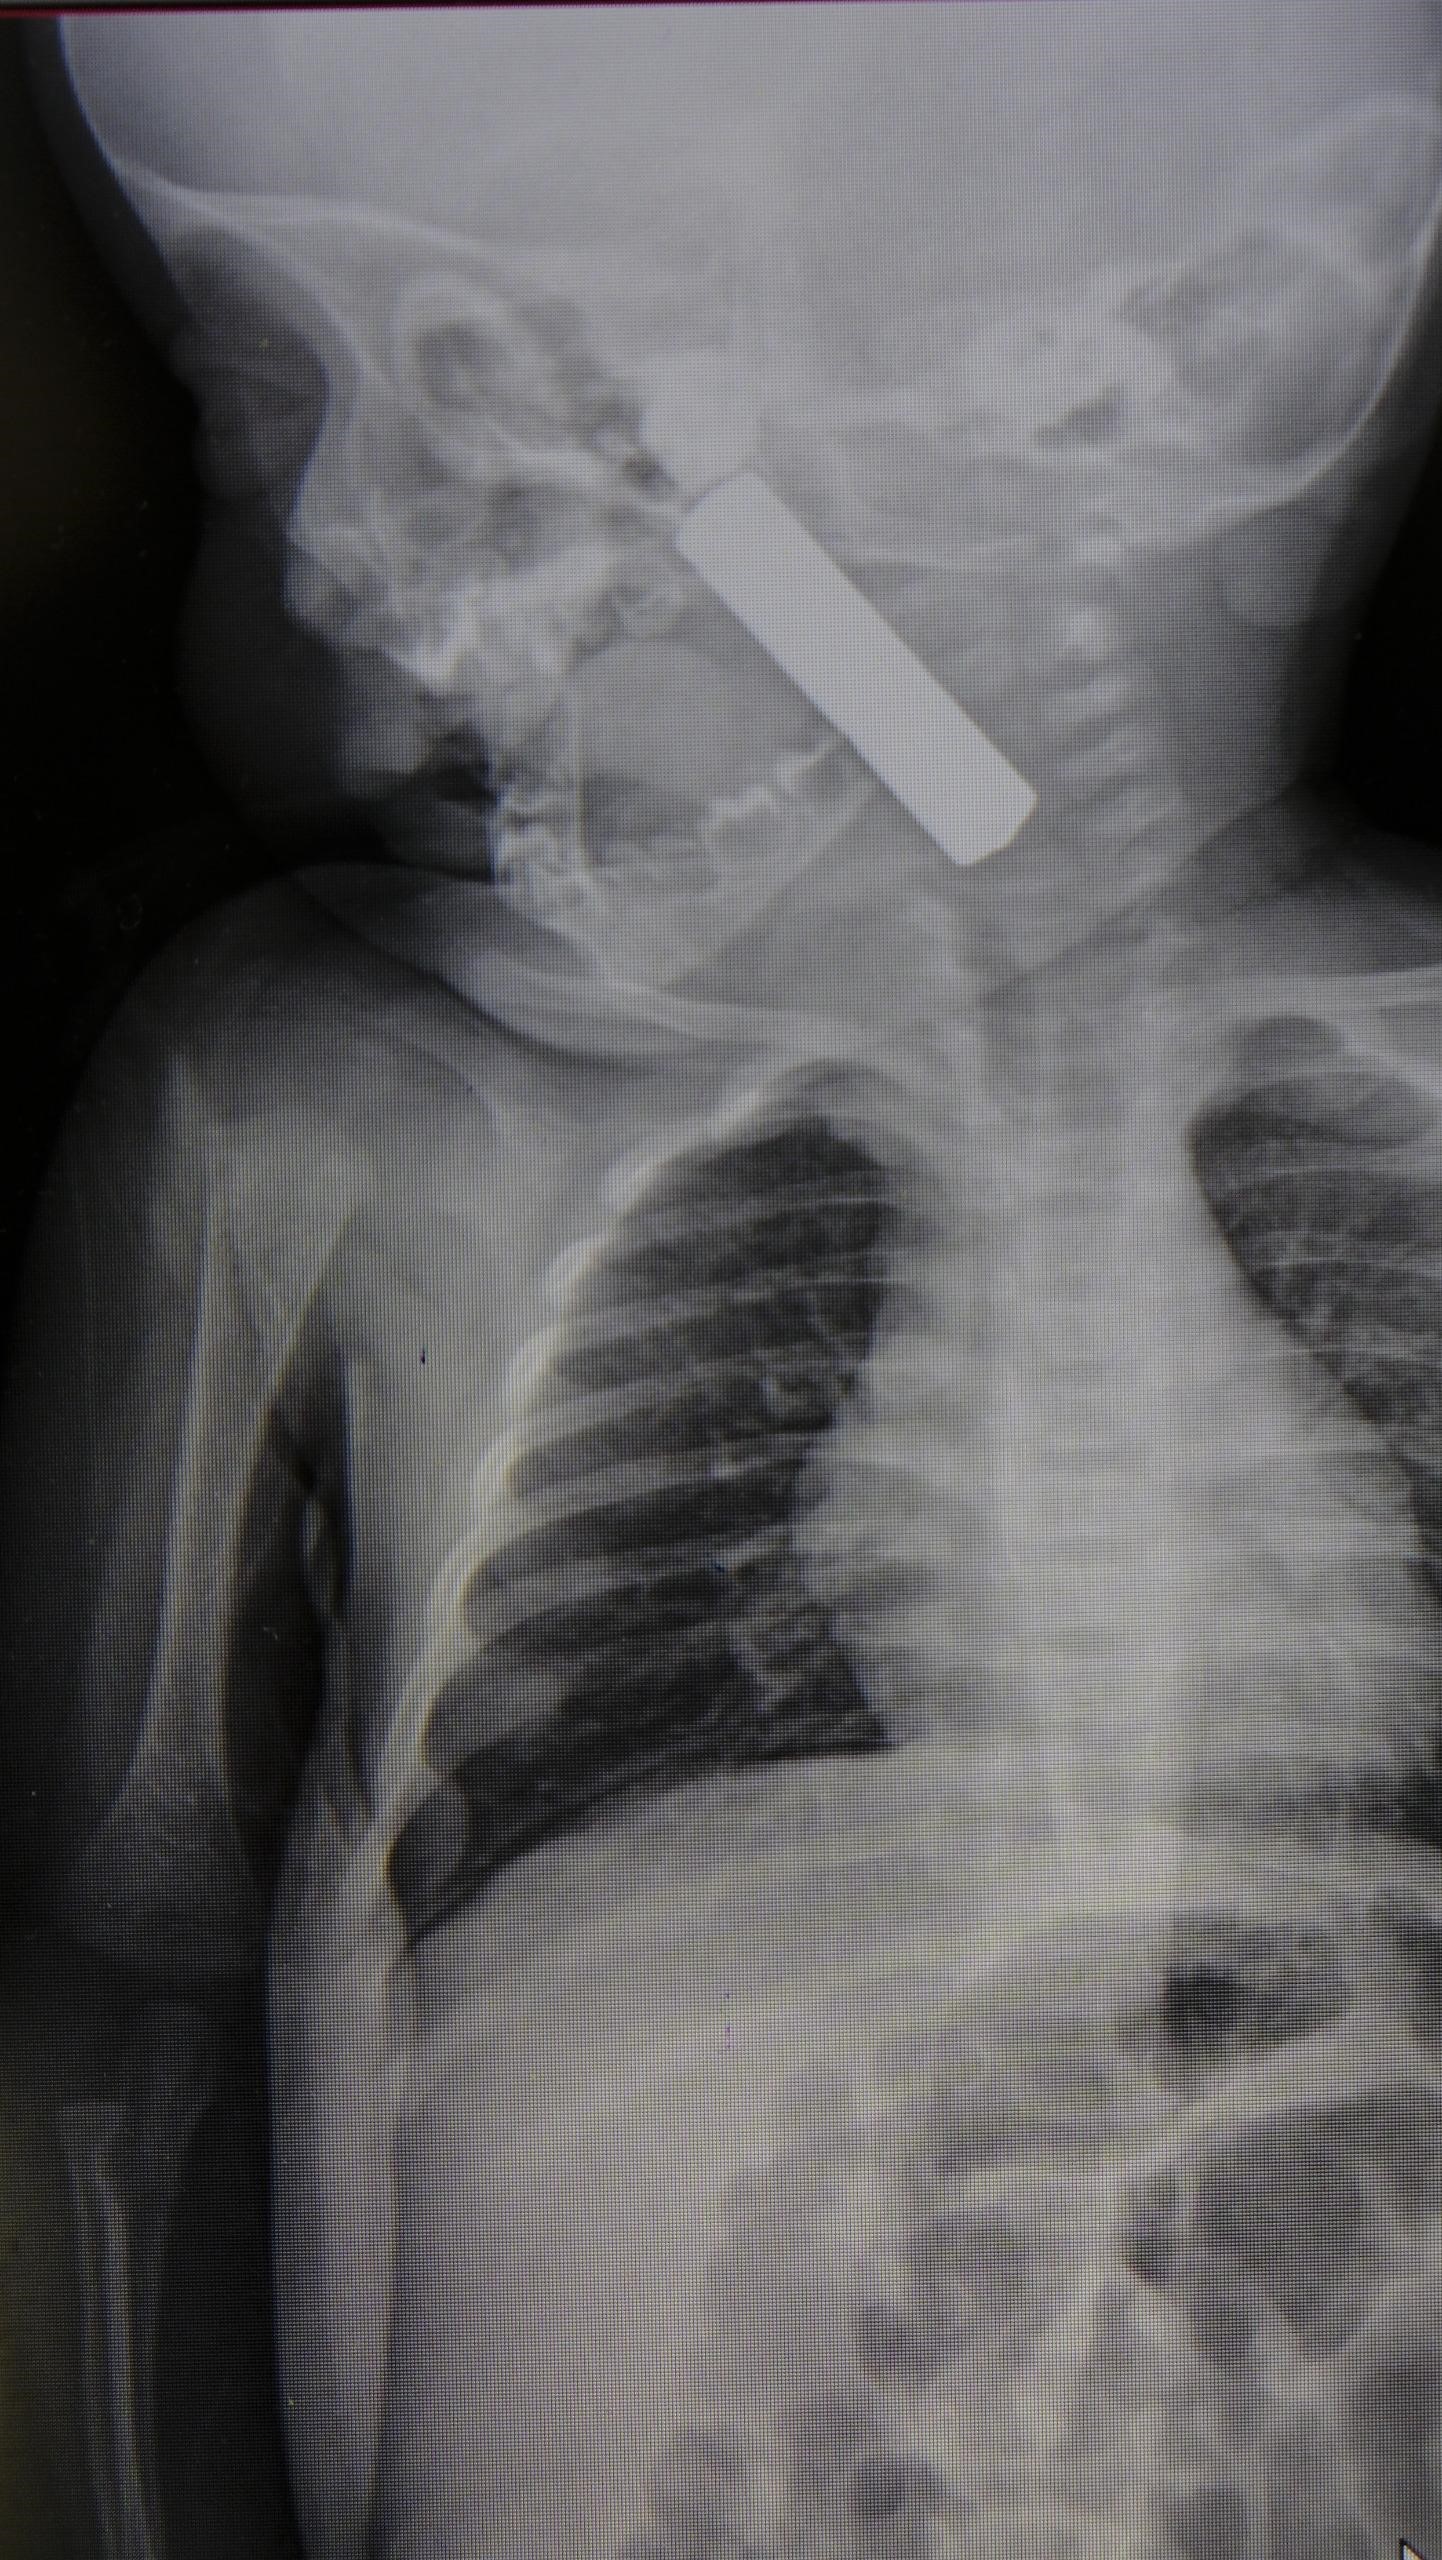

"Acil polikliniğimize kusma şikayeti ile 6 aylık bir kız bebek getirilmiş ve bize haber verildi. Biz de vakit kaybetmeden geldik, hastamızı gördük. Yapılan tetkikler sonucunda, ağız tabanına oturan ve yemek borusunun birinci darlığına kadar uzanan, kumanda pili dediğimiz bir pille karşılaştık. Filmde ve muayenede bunu gördük. Hastayı ilk gördüğümüzde bayağı siyanotik durumda, solunum sıkıntılıydı ve oksijen satürasyonu 90 civarındaydı. Böyle olunca bir an önce beklemeden hızlı bir şekilde ameliyathaneye götürdük. Orada ameliyathanedeki anestezi uzmanlarımız ve personel bize yardımcı oldu, hasta hızlı bir şekilde entübe edildi. Ondan sonra da laringoskop ve magill forseps dediğimiz malzemelerimizle bu yabancı cismi çıkarmış olduk. Bir an evvel müdahale ettik, iyi ki müdahale ettik, orada ağız tabanında, özellikle ön kısmında hasar oluşmuştu. Müdahale sonrasında da hastanın solunum problemleri bir süre devam etti, bu yüzden 24 saat takip ettik. Herhangi bir problem oluşmayınca 24 saat sonra kontrole gelmek üzere hastayı taburcu ettik"